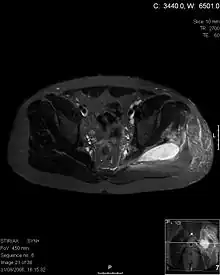

| Transverse T2 magnetic resonance imaging section through the hip region showing abscess collection in a patient with pyomyositis. | |

CT exam showing a multiloculated fluid collection in the left gluteus minimus muscle found to be a staph aureus pyomyositis in a 12-year-old healthy boy.

Coronal T2 weighted fat suppressed image showing a multiloculated fluid collection in the left gluteal musculature due to tropical pyomositis in a 12-year-old boy.